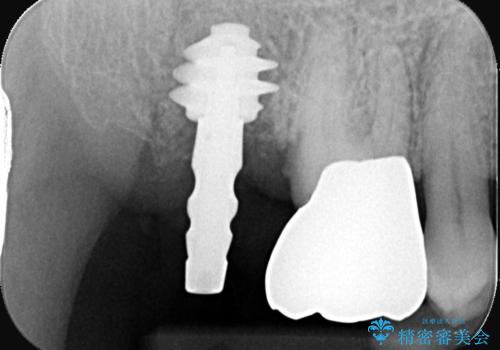

- 当院にて根管治療を行いましたが、病変の改善が得られなかったため、インプラント治療を行う方針といたしました。

抜歯即時埋入の適応と判断し、抜歯当日にインプラント埋入を行う「抜歯即時埋入」にて処置を実施しました。